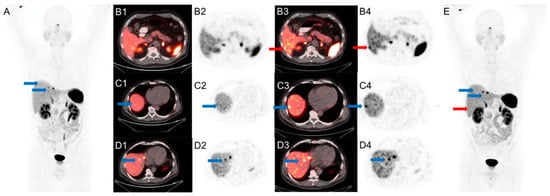

An example is shown in Figure 3.

Figure 3.

A 59-year-old man with metastatic small bowel NET, referred for subsequent treatment strategy after small bowel resection. Conventional PET/CT was performed first at 85 min after injection of 4.5 mCi of 68Ga-DOTA-TATE. SiPM-based PET/CT was performed second at 110 min after injection. Red arrows mark an additional lesion seen in the right lobe of the liver only on SiPM-based PET/CT (B3,B4,E) not on conventional PET/CT (A,B1,B2). Blue arrows mark liver lesions seen on conventional PET/CT (A,C1,C2,D1,D2) but more conspicuous on SiPM-based PET/CT (C3,C4,D3,D4,E).